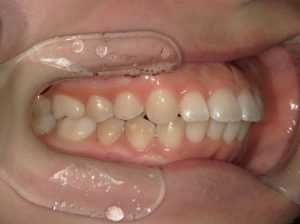

治療前→治療後(右側方)

治療前→治療後(左側方)

左側の第二小臼歯部と第二大臼歯部の鋏状咬合(ハサミのようにすれ違っているかみ合わせ)を改善しました。